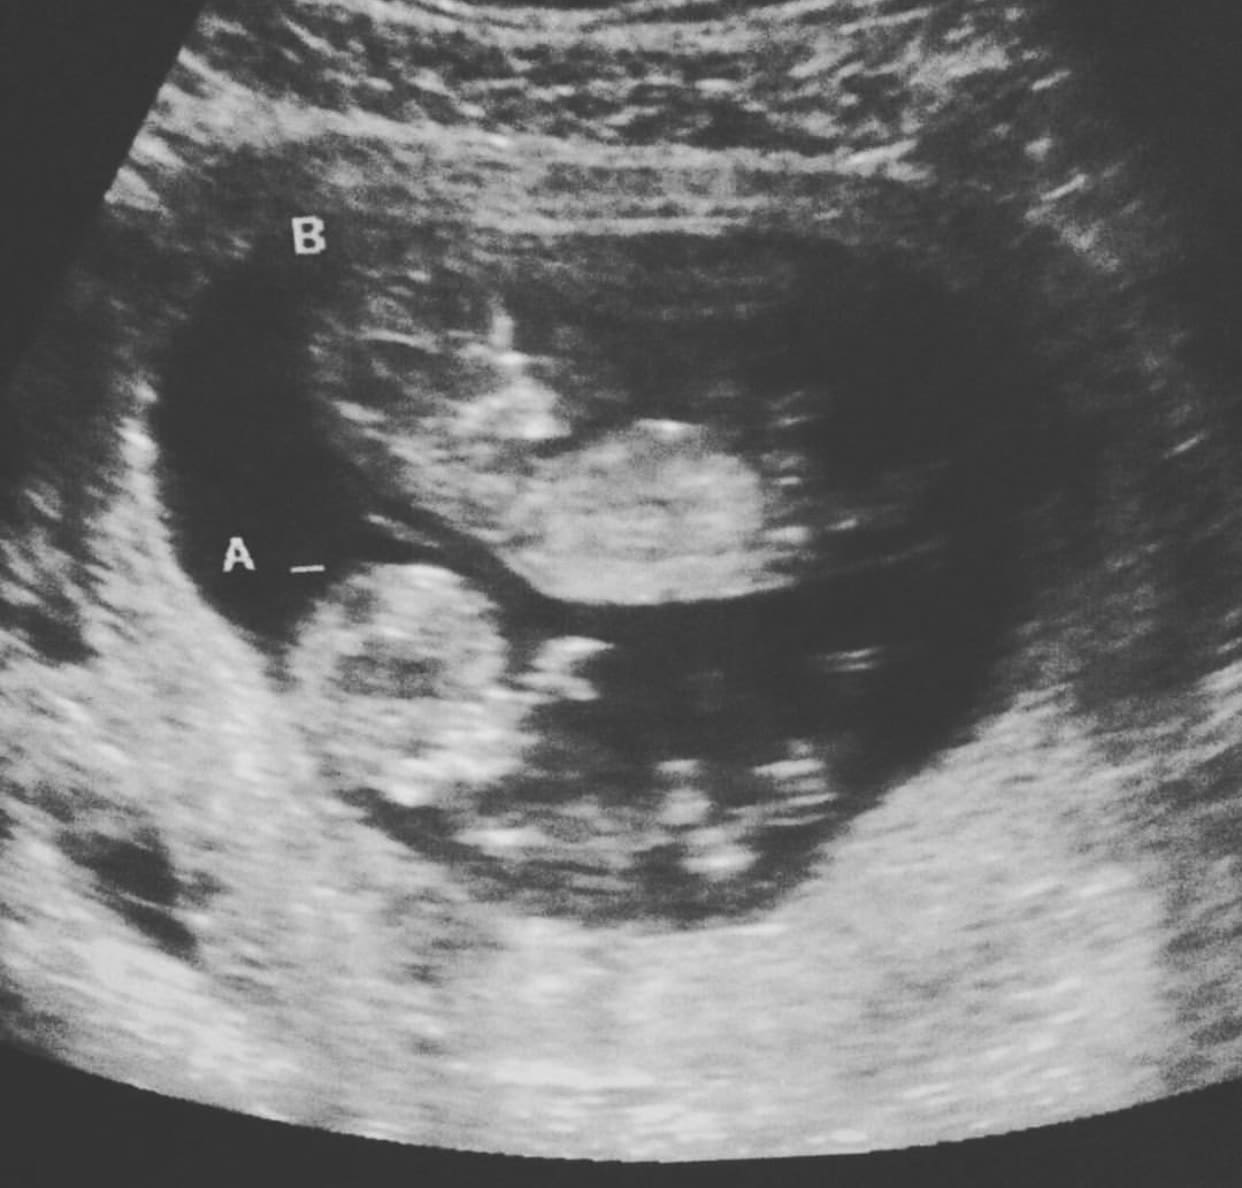

Ultrasound Photos at 14 Weeks Pregnant With Twins